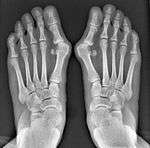

It is leaning of the first metatarsal bone away from the second metatarsal and towards the opposite foot (Fig. 1). As it leans over, its head sticks out to form the bunion bump and it also widens the forefoot to cause shoes feeling too tight. Thus when bunion pain becomes unmanageable, surgical correction is to narrow the forefoot by repositioning of the first metatarsal head back to its normal position. This can be done by osteotomy (bone-breaking), soft tissue (non-osteotomy) or fusion techniques.

Syndesmosis procedure addresses specifically the two fundamental problems of metatarsus primus varus deformity that gives rise to the bunion deformity. They are leaning and instability of the first metatarsal bone . Syndesmosis procedure uprights the leaning first metatarsal bone with strong binding sutures between it and the second metatarsal bone (Fig. 2) and then also stabilizes it uniquely by creating a fibrous connecting bridge between these two bones (Fig. 3,4). First metatarsal bone can be readily realigned is because by definition of the metatarsus primus varus deformity its first metatarsal is abnormally loose and mobile.